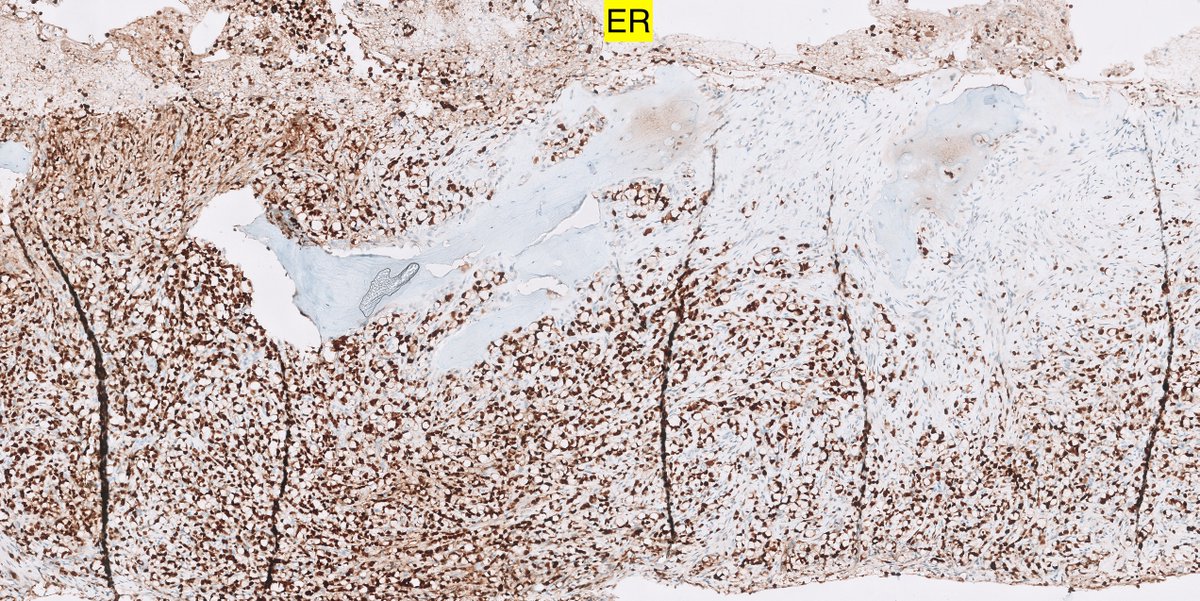

3/ #IHCpath

7/ So indeed this was a metastatic breast carcinoma and the answer and the problem lies in the non-specificity of the SP24 antibody as highlighted buy several of you

more specifically metastatic lobular carcinoma

8/ Fun fact

Did you know that the well-known prostate-specific IHC marker NKX3.1 is positive in 25-28% av lobular breast carcinomas also? Say what